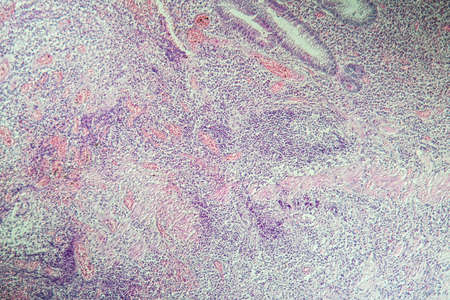

Squamous cell carcinoma diseased tissue under the microscope 100x

Squamous cell carcinoma of the uterus, light micrograph, photo under microscope